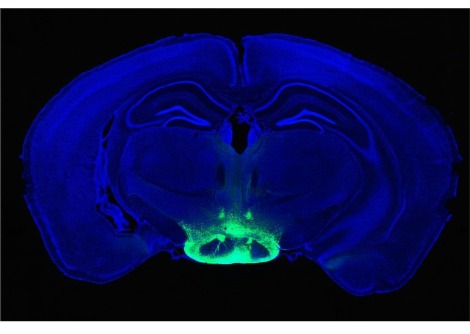

أظهر المختبر أن خمسة خيوط من microRNA تنظم إنتاج هذا الهرمون - والتي توجد في الكروموسوم 21 - معطلة. هذا الكروموسوم الزائد يؤدي بعد ذلك إلى تشوهات في الخلايا العصبية التي تفرز GnRH. تم تأكيد هذه النتائج على المستويين الجيني والخلوي. تمكن علماء Inserm من إثبات أن النواقص المعرفية والشمية التي لوحظت في الفئران كانت مرتبطة ارتباطًا وثيقًا بإفراز GnRH المختل وظيفيًا.

تمكن علماء Inserm بعد ذلك من إثبات أن استعادة وظيفة نظام GnRH الفسيولوجية تستعيد الوظائف الإدراكية والشمية في الفئران ثلاثية الذرات.

لذلك قرر الباحثون اختبار فعالية علاج GnRH النابض على العجز الإدراكي والشمي ثلاثي الزوايا في الفئران ، باتباع بروتوكول مماثل لتلك المستخدمة في البشر. بعد 15 يومًا ، تمكن الفريق من إثبات استعادة الوظائف الشمية والمعرفية في الفئران.

من وجهة النظر السريرية ، زاد الأداء المعرفي في 6 من 7 مرضى مع تمثيل ثلاثي الأبعاد أفضل ، وفهم أفضل للتعليمات ، وتحسين التفكير ، والانتباه ، والذاكرة العرضية. ومع ذلك ، لم يكن للعلاج تأثير على القدرة على الشم. تم تأكيد هذه التدابير لتحسين الوظائف المعرفية من خلال تصوير الدماغ الذي أجراه قسم CHUV لعلوم الأعصاب السريرية ، والذي كشف عن زيادة كبيرة في الاتصال الوظيفي.